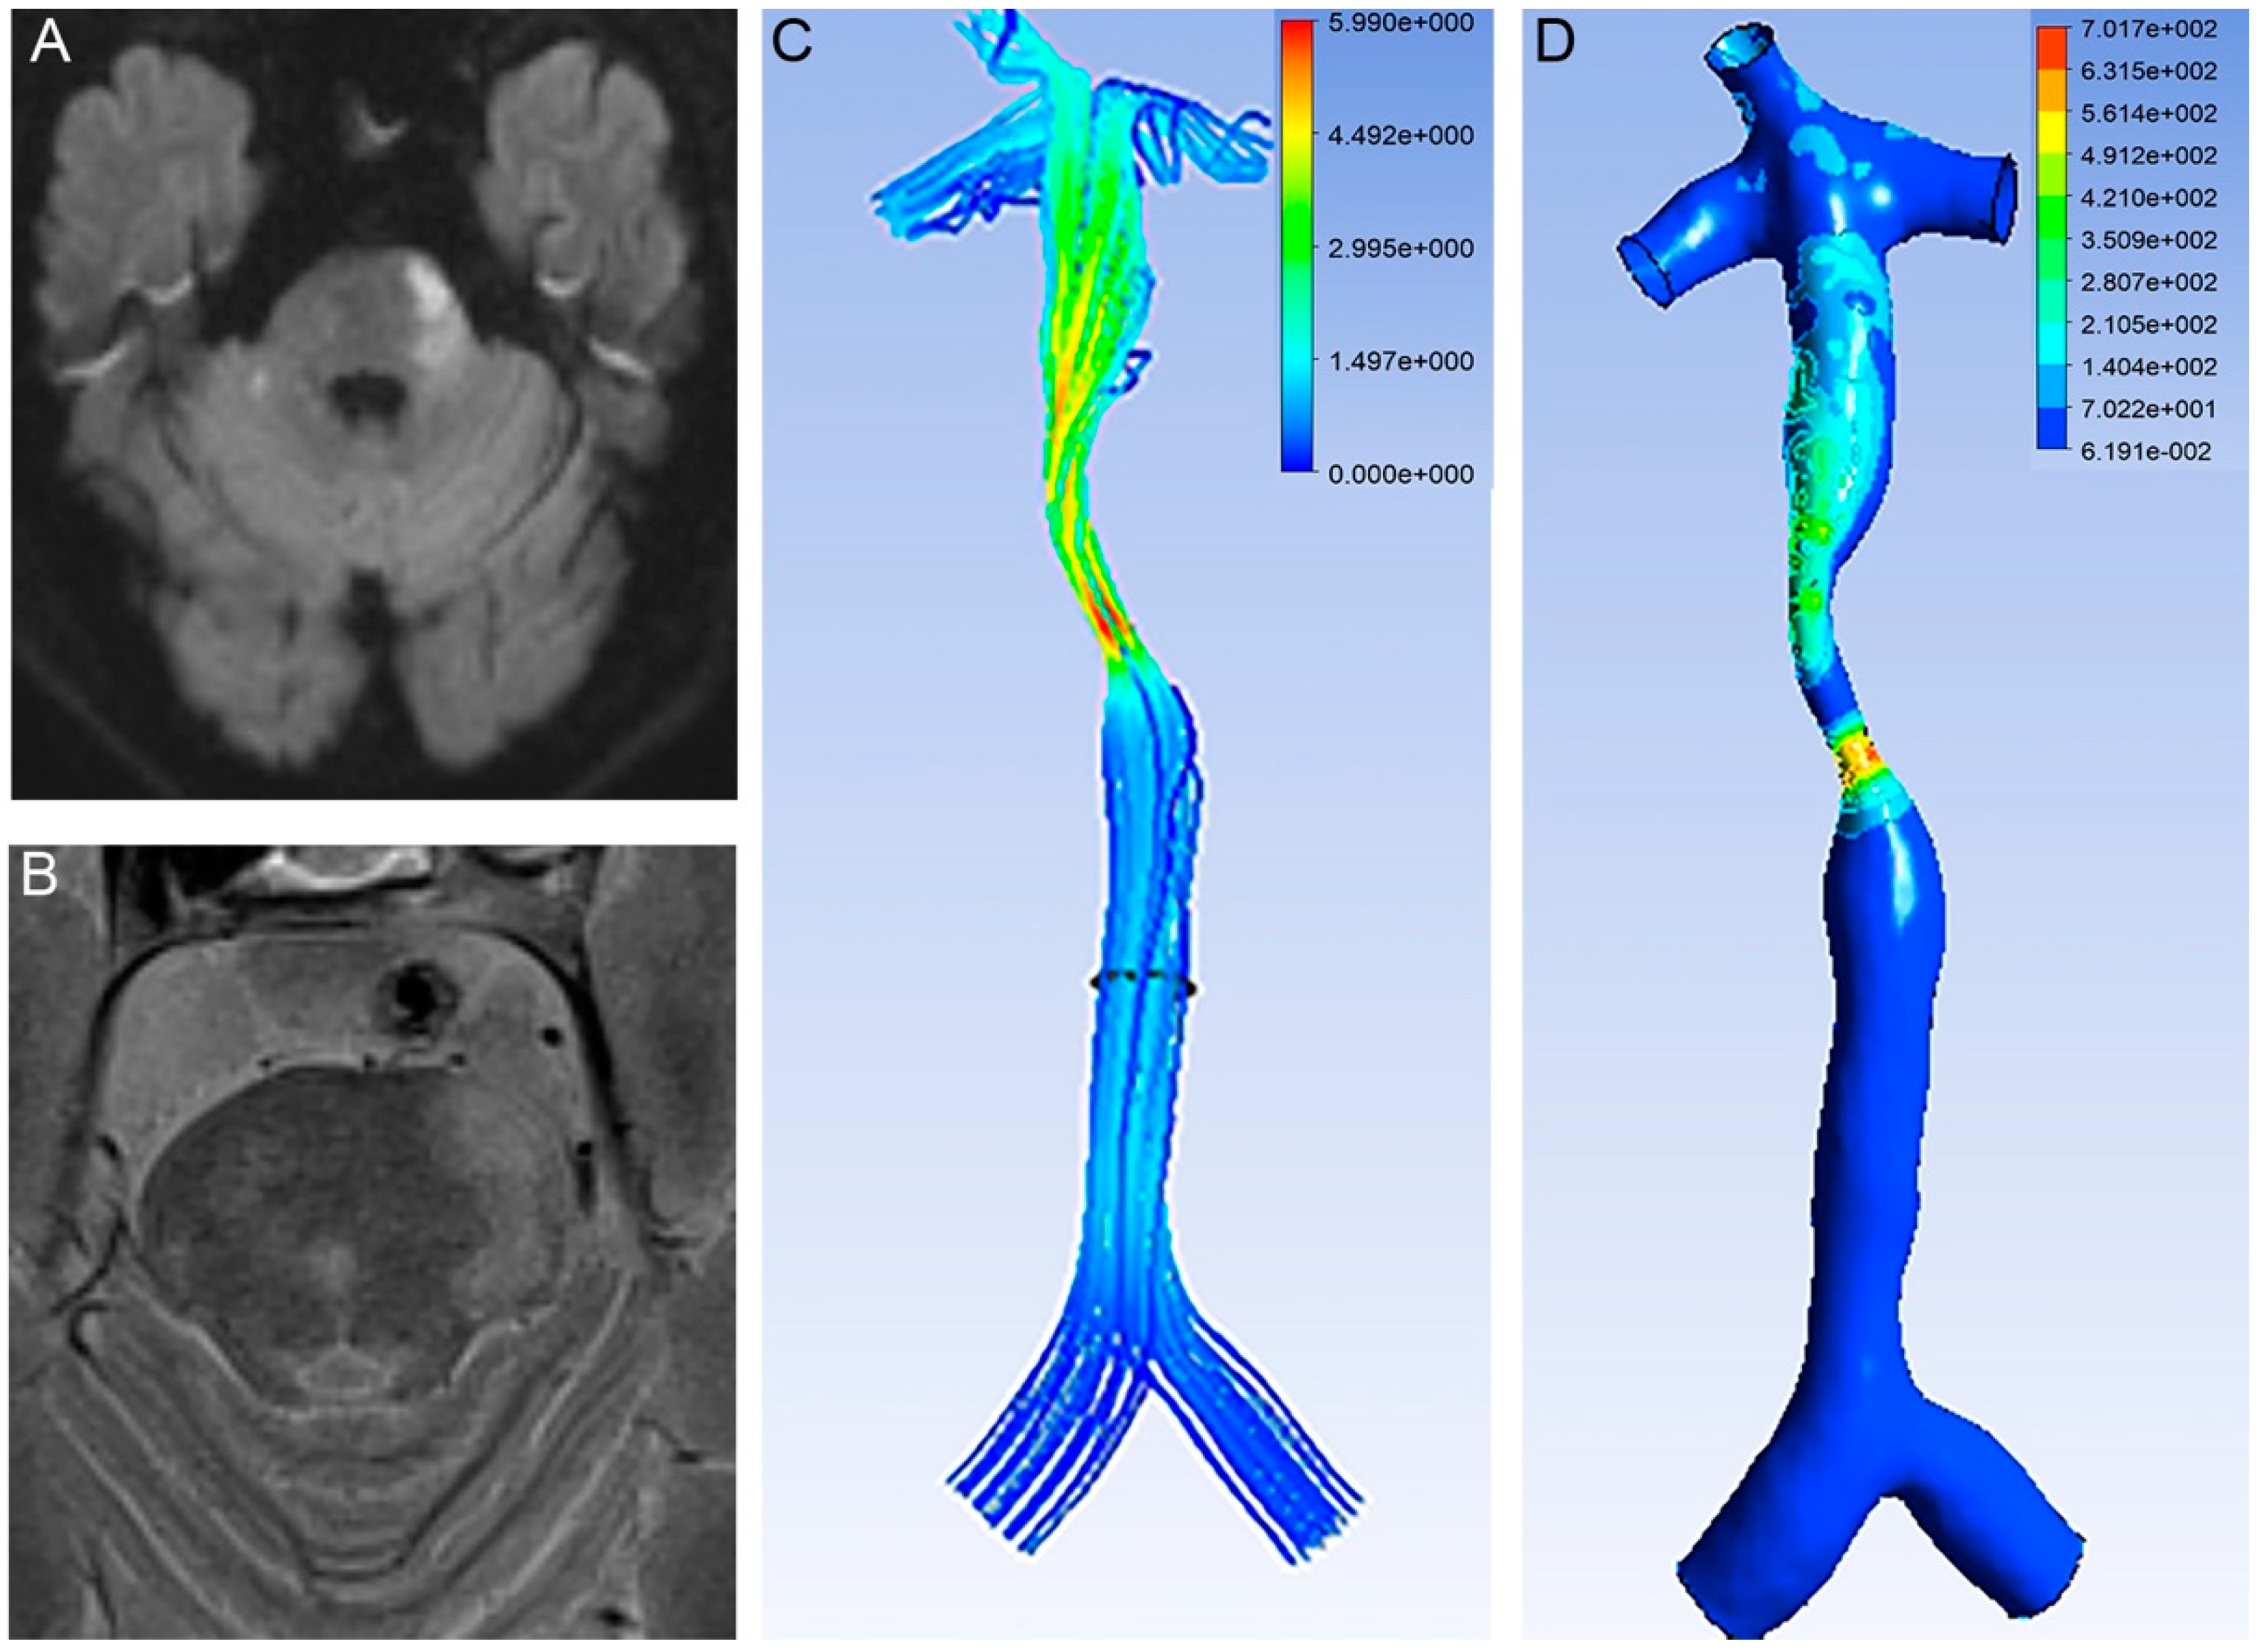

2.3. Calculation of the CFD

| Proximal WSS | 8.68 ± 17.60 | 8.07 ± 4.55 | 0.014 |

| Distal WSS | 48.62 ± 147.26 | 103.78 ± 522.40 | 0.567 |

| WSS ratio | 9.88 ± 21.12 | 16.04 ± 70.63 | 0.557 |

| Proximal velocity | 0.34 ± 019 | 0.38 ± 0.12 | 0.275 |

| Distal velocity | 0.90 ± 1.31 | 1.05 ± 2.04 | 0.858 |

| Velocity ratio | 2.49 ± 2.85 | 2.91 ± 5.54 | 0.811 |